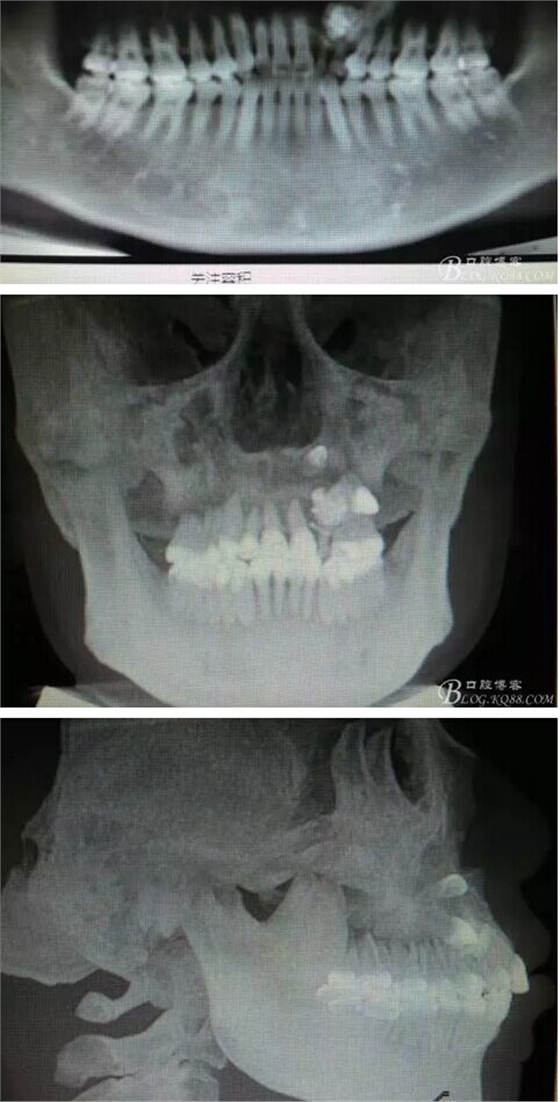

圖1。術前的CBCT影像檢查:22位于鼻底下方,23位于24、25的根方。左側(cè)乳Ⅱ、Ⅲ根方顯示囊性改變,囊腔內(nèi)大量致密鈣化團塊,密度高。